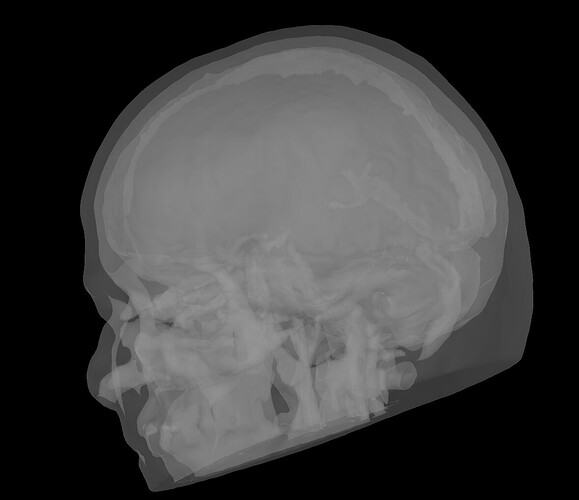

which does not really seem right. I have tried plotting in Matlab directly, suspecting a display issue, but, while if I plot the compact surface within the FEM (by exporting it in Matlab and selecting only the tissue labelled as compact), I get the right skull-like structure:

when I then scatter the vertices of the brainstorm extracted surface, I get again: